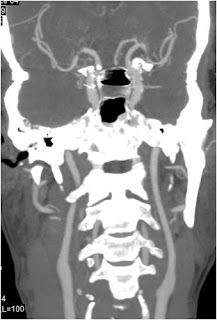

MIP Coronal

MIP Sagital

MIP Curve

MIP AVA Teknik

MIP Vascular